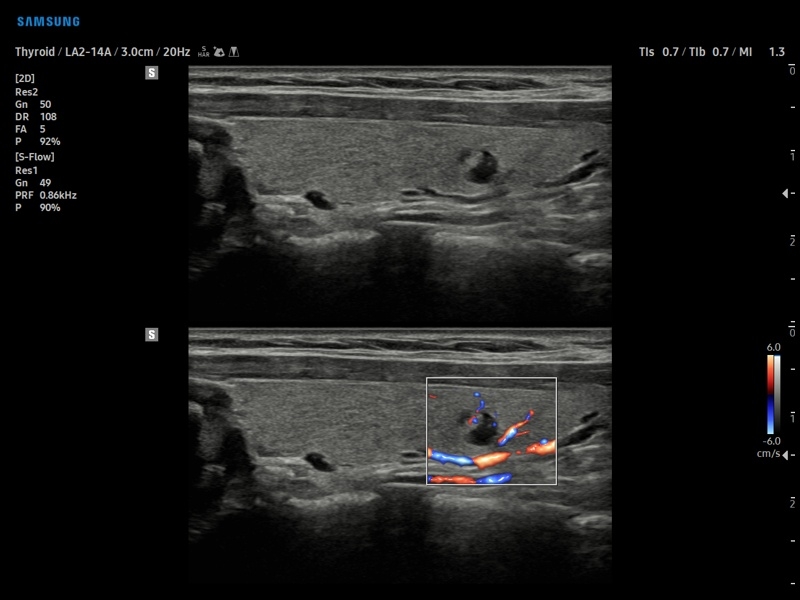

• S-Detect для исследования молочной железы и щитовидной железы

• МодульS-Detect Thyroid- программа автоматического обнаружения образований и анализа щитовидной железы, измерение и классификация по системе системе TI-RADS.

• Модуль S-Detect Thyroid - программа автоматического обнаружения образований и анализа щитовидной железы, измерение и классификация по системе системе TI-RADS.